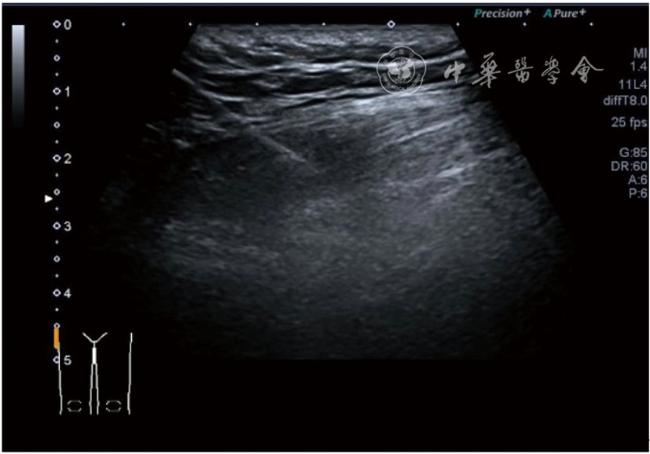

4.神经卡压液压松解加药物注射治疗。膝关节神经卡压主要涉及膝内上支、膝外上支、膝内下支、髌下支。可根据神经支配区域的临床检查确定卡压神经。临床上隐神经髌下支卡压常见。隐神经髌下支从隐神经发出后穿缝匠肌至膝内前下方,与深筋膜紧密相连(图24)。隐神经髌下支卡压出现膝关节内下侧酸痛、麻木,胫骨内侧髁压痛阳性,Tinel征阳性,局部皮肤痛觉减退。确定诊断后可行隐神经髌下支液压松解。患者平卧位,膝关节屈曲30°,下面垫一软枕。一般选用10 MHz以上超声探头,穿刺区域常规消毒,探头涂抹耦合剂后套入无菌手套碘伏消毒或使用无菌耦合剂。首先扫查神经短轴切面,确定神经后旋转为长轴切面引导注射。选用25G穿刺针头,抽吸0.5%利多卡因4 ml+地塞米松3 mg,从近端穿刺,沿神经表面纵轴方向,确定针尖在神经膜外后推注药物进行松解,注射完毕后拔出针头(图25),局部压迫2分钟,创可贴覆盖。

图25 超声引导下隐神经髌下支卡压液压松解加药物注射治疗